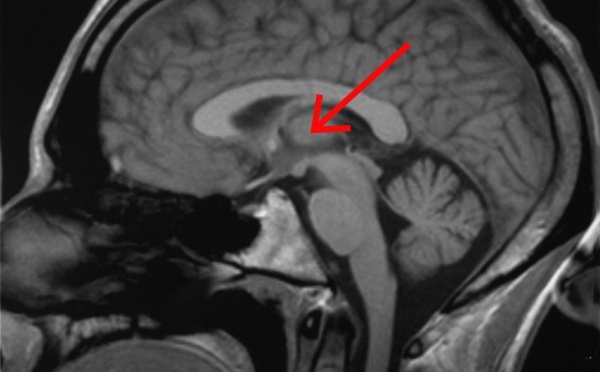

El tálamo filtra la información visual para formar las imágenes que percibimos - 22/05/2012

Un equipo de investigadores de la Universidad de La Coruña está investigando los mecanismos por los cuales el encéfalo (parte superior y de mayor masa del sistema nervioso) consigue darle forma a las imágenes que capta la retina o tejido sensible a la luz situado en la superficie interior del ojo. Los resultados de sus estudios han revelado que una estructura cerebral conocida como tálamo es la encargada de filtrar la información que percibimos para que finalmente la corteza cerebral genere las imágenes que vemos.